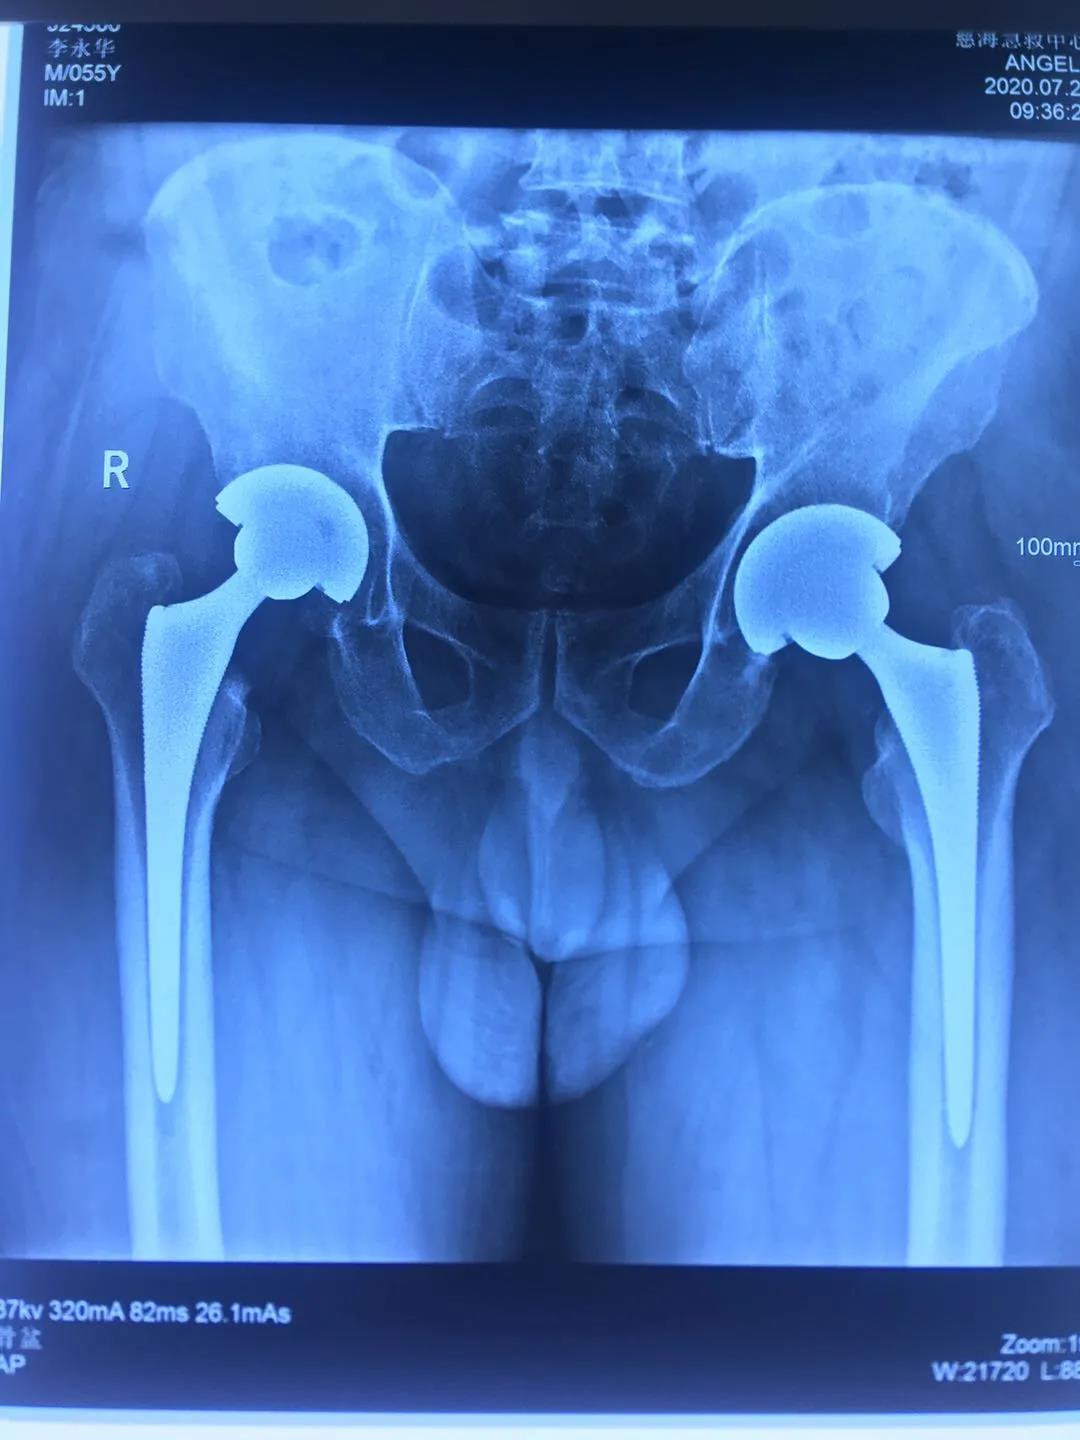

患者一年前雙側(cè)髖疼痛,到骨科就診,確診為股骨頭壞死,由于左髖關(guān)節(jié)痛疼較重給予行左髖關(guān)節(jié)置換,術(shù)后恢復(fù)良好。今年右髖關(guān)節(jié)痛疼加重再次住院,入院后完善相關(guān)檢查,根據(jù)患者病情,征得患者及家屬同意,順利施行了右髖關(guān)節(jié)置換術(shù),術(shù)前片子提示患者骨盆傾斜較重,術(shù)前評估設(shè)計術(shù)中假體植入角度,術(shù)后完美恢復(fù)雙下肢長度與雙側(cè)髖關(guān)節(jié)旋轉(zhuǎn)中心,患者非常滿意,目前患者情況良好,已出院。

術(shù)后復(fù)查拍片